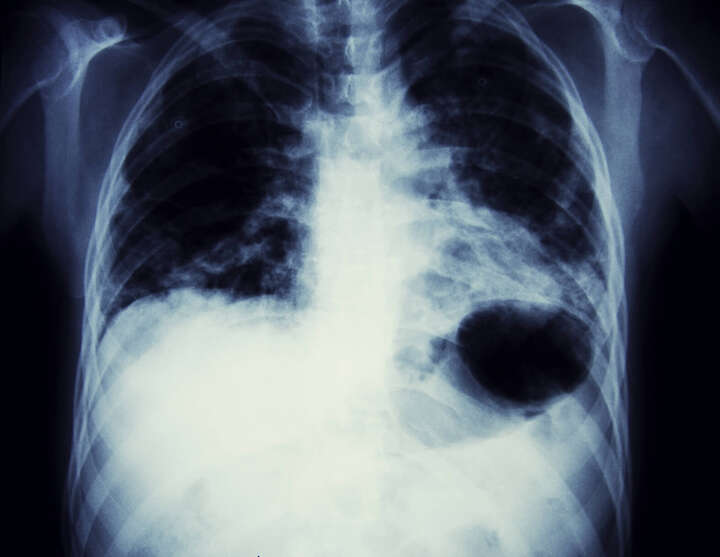

qTrack funciona con

Inteligencia Artificial (IA) a través del

procesamiento rápido de resultados. Utiliza algoritmos de aprendizaje profundo para analizar los rayos X y detectar incluso los nódulos más pequeños. Además de detectar la enfermedad la aplicación también identifica otras 6 anormalidades incluyendo

Se cree que los cánceres de pulmón comienzan como áreas de cambios anormales y los primeros cambios ocurren en los genes de las mismas células ocasionando que crezcan rápidamente. Las células pueden lucir un poco anormales si se observan con un microscopio, pero en este punto no forman una

masa o

tumor, por lo que no se pueden ver con rayos X y no causan síntomas.

Con el paso del tiempo estos cambios pueden progresar hasta convertirse en un verdadero cáncer y en este punto,

las células cancerosas pueden producir sustancias químicas que contribuyan a la formación de nuevos vasos sanguíneos en las áreas vecinas. Estos vasos sanguíneos nutren a las células cancerosas que pueden continuar creciendo para formar un

tumor lo suficientemente grande para verse en estudios por imagen, como los rayos X.